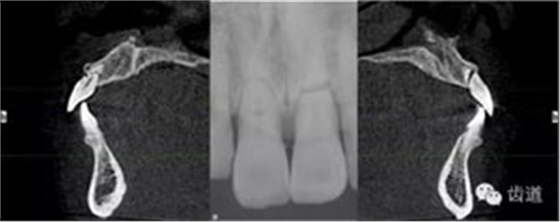

放射檢查:11,21根中三分之一至根尖三分之一處折斷。

術(shù)前放射片